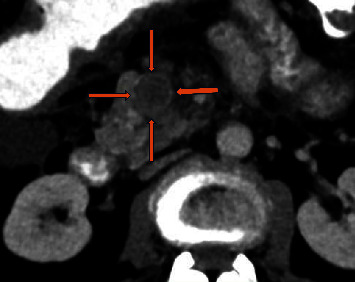

缺血性肠病被认为是厌氧菌感染的高危因素,因为缺血性肠道是厌氧菌生长的理想场所。在此,我们介绍了一例结肠癌晚期患者的病例,该患者罕见地出现了消化道出血和菌血症,病因是一种罕见的厌氧革兰阳性菌--副梭状芽孢杆菌。该患者在慢性肠系膜上静脉-门静脉肿瘤血栓形成和异位静脉曲张破裂的情况下曾多次出现血崩,而菌血症是动脉缺血和静脉充血共同导致的肠道缺血的意外并发症。

Ischemic bowel disease is considered a high-risk factor for infection from anaerobic bacteria, as the ischemic bowel is the perfect ground for their development. Herein, we present the case of an advance stage colon cancer patient with a rare cause of gastrointestinal bleeding and bacteremia due to Clostridium paraputrificum, a rare anaerobic Gram-positive bacterium. The patient had presented with several episodes of hematochezia in the context of chronic superior mesenteric-portal vein tumor thrombosis and rupture of ectopic varices, and the bacteremia was an unexpected complication of the bowel ischemia due to a combination of arterial ischemia and venous congestion.